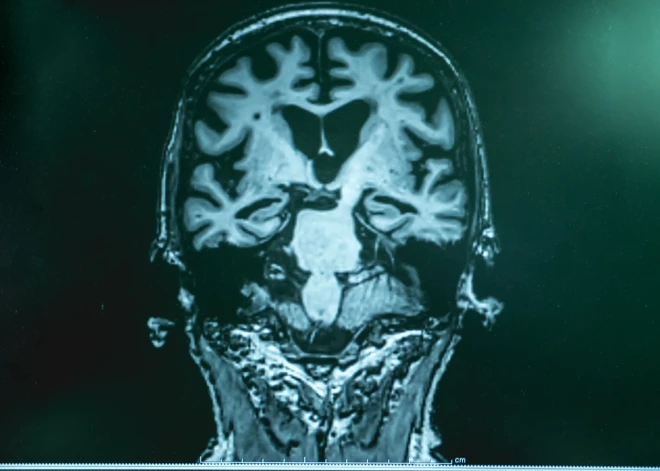

Taču, pēc visām pazīmēm, ar atmiņas un domāšanas problēmām viņam vajadzēja saskarties jau gadu desmitiem agrāk. Kad ārsti pēc nāves pārbaudīja viņa smadzenes, atklāja, ka tajās ir daudz beta amiloīda un tau - divu olbaltumvielu veidi, kas uzkrājas Alcheimera slimnieku smadzenēs.

Veicot ģenētisko analīzi, atklājās, ka vīrietim ir reti sastopamas izmaiņas gēnā, kas kodē olbaltumvielu, kas palīdz nervu šūnām sazināties. “Šajā gadījumā bija skaidrs, ka izmaiņas konkrētajā gēnā, uzlabo vīrieša smadzeņu darbību. Tas paver iespējas palīdzēt pacientiem nākotnē,” apstiprināja Dr. Džozefs Arboleda-Velaskess, Hārvarda universitātes oftalmoloģijas asociētais profesors.